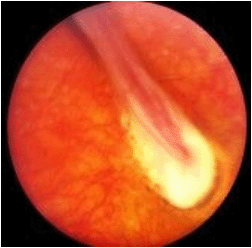

男性,20岁,双眼视物不清就诊,检查:眼前段(-),眼底检查如图,符合该病的描述是()

-